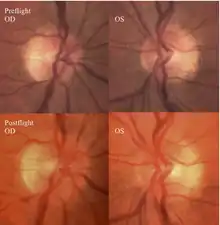

The first U.S. case of visual changes observed on orbit was reported by a long-duration astronaut that noticed a marked decrease in near-visual acuity throughout his mission on board the ISS, but at no time reported headaches, transient visual obscurations, pulsatile tinnitus or diplopia (double vision). His postflight fundus examination (Figure 1) revealed choroidal folds below the optic disc and a single cotton-wool spot in the inferior arcade of the right eye. The acquired choroidal folds gradually improved, but were still present 3 year postflight. The left eye examination was normal. There was no documented evidence of optic-disc edema in either eye. Brain MRI, lumbar puncture, and OCT were not performed preflight or postflight on this astronaut.[5]

The sixth case of visual changes of an ISS astronaut was reported after return to Earth from a 6-month mission. When he noticed that his far vision was clearer through his reading glasses. A fundus examination performed 3 weeks postflight documented a grade 1 nasal optic-disc edema in the right eye only. There was no evidence of disc edema in the left eye or choroidal folds in either eye (Figure 13). MRI of the brain and eyes days postflight revealed bilateral flattening of the posterior globe, right greater than left, and a mildly distended right optic nerve sheath. There was also evidence of optic-disc edema in the right eye. A fundus examination postflight revealed a "new onset" cotton-wool spot in the left eye. This was not observed in the fundus photographs taken 3 weeks postflight.[5]

The seventh case of visual changes associated with spaceflight is significant in that it was eventually treated postflight. Approximately 2 months into the ISS mission, the astronaut reported a progressive decrease in his near and far acuity in both eyes. The ISS cabin pressure, CO2 and O2 levels were reported to be within normal operating limits and the astronaut was not exposed to any toxic substances. He never experienced losses in subjective best-corrected acuity, color vision or stereopsis. A fundus examination revealed a grade 1 bilateral optic-disc edema and choroidal folds (Figure 15).[5]